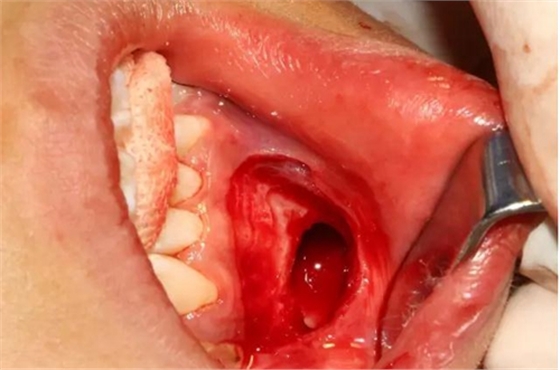

切開、翻瓣

去除骨皮質,暴露牙冠大部分